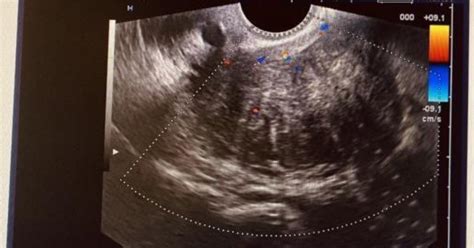

- Consultație ginecologică și ecografie - Aceasta este prima metodă de investigare, prin care se identifică prezența fibroamelor și se determină dimensiunea, localizarea și numărul acestora. Cea mai eficientă metodă de diagnostic este însă prin ecografie transvaginală, care poate identifica orice formațiune tumorală, chiar și de mici dimensiuni.